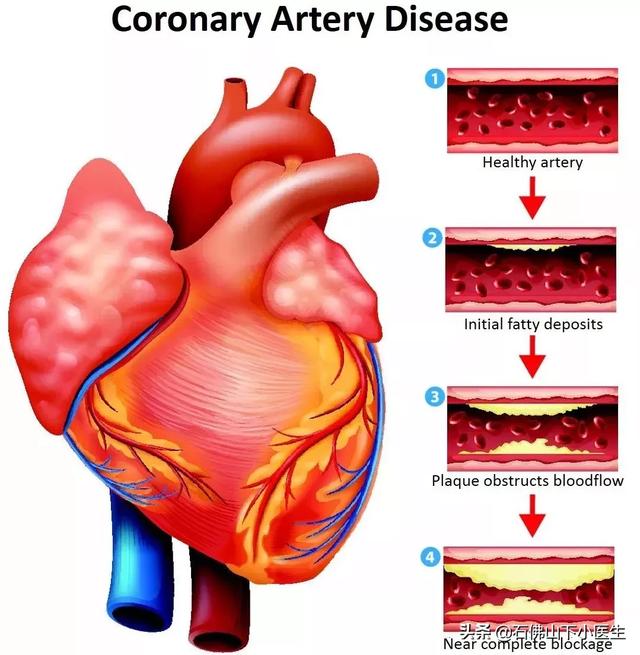

私たちは皆、多かれ少なかれ知っているはずだ。冠状動脈性心臓病とは、主に心臓の冠状動脈が狭くなる病気である。心臓に血液を供給する血管の狭窄は、心筋虚血や心筋壊死を引き起こす可能性があり、この狭窄を解消して冠動脈への血液供給を回復させるために、治療法のひとつは次のようなものである。何か支えとなるものを持っていく。それこそが、今、私たちが話しているブラケットなのだ。

でもね。もし冠動脈の内腔が狭くなっていれば、心筋の酸素需要が増大しても、冠動脈の血液供給はそれに応じて増大することができず、心筋虚血となり、心筋虚血が長引くと心筋壊死を引き起こし、心臓発作の引き金となる。急性心筋梗塞は、不整脈、心原性ショック、心不全、心室壁破裂などの重篤な結果をもたらすこともあるので、冠動脈性心疾患は非常に深刻に受け止めなければならない。

冠状動脈は心臓に血液を供給する主な動脈で、年齢、三高、慢性病、悪習慣などの影響を受けて、心臓に血液を供給する冠状動脈も他の動脈と同じように、アテローム性動脈硬化症、狭窄、プラークなどの問題が現れる、冠状動脈の狭窄が50%以上の場合、通常、心臓の血液供給と酸素供給が大きな影響を受けると考えられ、このような場合、冠状動脈性心臓病と診断することができます。このような場合、冠動脈性心疾患と診断することができる。

(2) 動脈硬化:冠動脈性心疾患とは、血液中の脂質成分が内皮細胞の下に侵入し、炎症反応が起こり、動脈硬化性プラークが形成されることによって引き起こされる病気のことである。

(3) 心臓病:人がある年齢に達すると、実際、全身の多くの血管が動脈硬化を起こす可能性があるが、動脈硬化の狭窄がある程度に達した場合のみ、対応する臓器に明らかな影響を引き起こす。例えば、冠状動脈硬化症は、内腔の狭窄が50%以上であれば、冠状動脈硬化性心疾患と呼ぶことができ、心臓の機能に影響を与えるが、50%未満であれば、冠状動脈硬化症と呼ぶ。

- 冠動脈は、心臓そのものに血液を供給する動脈であり、動脈硬化、または私たちがよく呼ぶプラークである。冠動脈はプラークを生成し、プラークは徐々に大きくなり、心臓への血液と酸素が不足し、さまざまな症状を引き起こす。

一般に、冠動脈を塞いでいるプラークが50%以下であれば、冠動脈性心臓病とは呼ばず、冠動脈硬化症と呼び、現時点では比較的軽症であるが、将来的にはより危険である。

- それとともにプラークは徐々に大きくなり、冠動脈狭窄が50%を超えると冠動脈疾患と呼ばれ始める。

- 冠動脈の狭窄が50~70%以上になると、狭心症の症状が現れることがある。穏やかな状態では、患者は症状がないかもしれませんが、感情的な興奮、活動状況、心臓の酸素需要が増加すると、冠動脈は、狭窄のため、十分な酸素を供給することができません、この場合、血液不足、酸素不足のため、心臓は胸の締め付け感、前胸部痛の症状が現れます。これが安定狭心症です。

冠動脈性心疾患とは、冠動脈アテローム性動脈硬化性心疾患の略称であり、主に心臓に血液を供給する動脈である冠動脈のアテローム性動脈硬化によって引き起こされる。動脈にアテローム性動脈硬化症が起こると、動脈の内表面にプラークが形成され、プラークが蓄積するほど動脈の直径が狭くなる。狭窄の程度が50%未満であれば、心筋への血液供給には影響しないので、一般的に症状はありませんが、50%以上になると、心筋への血液供給に影響を及ぼし、心筋の酸素消費量が増加しても、心筋が十分な酸素を得ることができず、心筋虚血、低酸素状態になると、胸部圧迫感、胸痛の症状が誘発され、これを狭心症と呼びますが、狭心症の症状は活動を停止すると徐々に緩和されます。狭窄の程度がさらに悪化したり、局所的なプラークの破裂、冠動脈の血栓閉塞によって心筋虚血が生じたりすると、狭心症の程度はさらに悪化し、緩和されない状態が続き、閉塞が解除されなければ心筋虚血壊死を引き起こし、ついには患者の突然死に至ることもあり、これが心筋梗塞と呼ばれるものです!